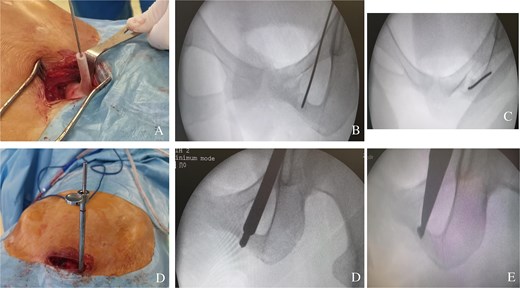

The patient received acetylsalicylic acid, with partial clinical improvement. The decision was made to perform a surgical drilling and curettage of the tumour with the help of a customized 3D-printed guide (Fig. 2A–C). The patient underwent surgery on a standard table, in supine position, under general anaesthesia. A mini-Pfannenstiel approach (on the pubic symphysis) was performed to expose the proximal and medial border of the left iliopubic ramus, which served as a fixed landmark for positioning the guide (Fig. 3A). Once the guide had been pinned in place, a K-wire was inserted in the direction of the tumour. A fluoroscopic check verified the K-wire positioning (Fig. 3B). A soft tissue protection instrument was used to guide the cannulated drill bit towards the tumour (Fig. 3C). Drilling and curettage of the lesion was performed under fluoroscopic control with anteroposterior, inlet, and outlet views of the pelvis (Fig. 3D and E). The anatomopathological examination confirmed the diagnosis of osteoid osteoma, which was completely resected. Pain disappeared in the immediate postoperative period. At 24-month follow-up, we did not note recurrence of the tumour (Fig. 4A and B). Written informed consent was obtained from the patient.

(A) Positioning the guide on the iliopubic ramus via a mini-Pfennestiel approach. (B) Anteroposterior fluoroscopic control of the correct position of the K-wire in the tumour. (C) Fluoroscopic inlet view showing the correct position of the K-wire in the tumour. (D) A soft tissue protection instrument as a guide for the cannulated drill. (E) Curettage of the tumour.